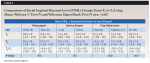

The mean overall changes of facial implant mucosal thickness (FIMT) from T1 to T2, facial implant mucosal level (FIML) from T0 to T3, and midfacial bone sounding (MFBS) from T1 to T3 were 1.2 ± 0.5 (1.6 to 2.9) mm, -0.4 ± 0.4 (-1.6 to 1.0) mm, and 6.0 ± 1.4 (4.0 to 8.5) mm, respectively (Table 2 through Table 4). Comparisons of tissue changes between different parameters (thick vs thin phenotype, V- vs U-shaped facial bone wall defect, and surgery with vs without full-thickness flap reflection) also are presented in Table 2 and Table 3. Regardless of phenotype, defect shape, or surgical technique, the mean FIMT values at T2 were comparable (2.3 mm to 2.4 mm), and all MFBS measurements at T3 were between 3 mm and 4 mm (Table 2 and Table 4). The mean FIML change of -0.4 mm and MFBS change of 6.0 mm translates to a mean vertical facial hard tissue gain of 5.6 mm.

The significance of a C-BG at the time of IIPP in maintaining facial mucosal level in the presence of a facial bone wall defect is also a point of discussion. Typically, it takes months for bone cells to migrate from the surrounding socket walls to encase or replace the grafted bone material within the extraction socket.23 Therefore, the initially grafted bone only serves as a matrix to support the soft tissue until vital bone formation occurs. During the early healing time, the most coronal portion of the bone at the facial entrance of the extraction socket will serve to maintain the FIML until grafted bone matures. In this study, facial contour bone grafting over the implant and facial bone wall defect (T1) resulted in a mean MFBS change of 3.5 mm ± 0.4 mm (T3), suggesting that the particulate bone graft material turned into solid, stable bone over time. It is interesting to note that regardless of tissue phenotype, defect shape, or whether the surgical procedure was done with or without flap reflection, all of the MFBS measurements at T3in all sites were between 3 mm and 4 mm (Table 3), indicating that the technique performed in this study could yield a predictable result. Moreover, because the platforms of the implants in this study were placed about 3 mm apical from the facial mucosal margin, the radiographic bone measurement from the implant platform (mean CBCT-FMBL [-0.7 mm]) and the bone sounding measurement (mean MFBS [3.5 mm]) confirmed that the facial bone was regenerated almost to the level of the implant platform. At T3, the mean FIML change of -0.4 mm and mean MFBS change of 6.0 mm also translate to the mean vertical facial hard tissue gain of 5.6 mm.

A thin soft-tissue phenotype has been associated with an increased risk of facial implant mucosal dehiscence (ie, recession).19,24,28 Numerous studies have shown the benefits of C-CTG simultaneous with IIPP.17,21,23,29,30 Thickening the FIMT not only can minimize facial mucosal recession, but it may also conceal the underlying implant and/or implant restorative materials. Moreover, thickening the facial mucosa may override the need for underlying facial bone support. A 1-year follow-up study on IIPP and C-CTG on maxillary anterior implants showed an average increase in FIMT of 1.4 mm (0.4 mm to 2.7 mm).29 In the present study, a comparable mean FIMT gain of 1.2 ± 0.5 (0.3 to 2.0) mm with C-CTG grafting was noted after a mean follow-up time of 8.9 (6 to 15) months. Irrespective of initial (T1) soft-tissue phenotype, the average resulting (T2) FIMT of both thick-tissue and thin-tissue phenotype groups was similar (2.3 ± 0.4 mm; Table 2), indicating that thin soft-tissue phenotype is likely to benefit more from this phenotype modification procedure. The changes in FIML and MFBS were comparable between thick and thin phenotype groups (Table 3 and Table 4).